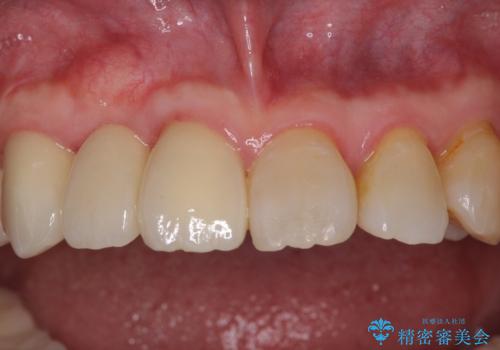

数多くの外科処置を行ったため、治療期間は長期間となりました。

一方、外科処置をしっかりと行ったことで、歯周病の状態は改善され、安定した状態にしあげることができました。